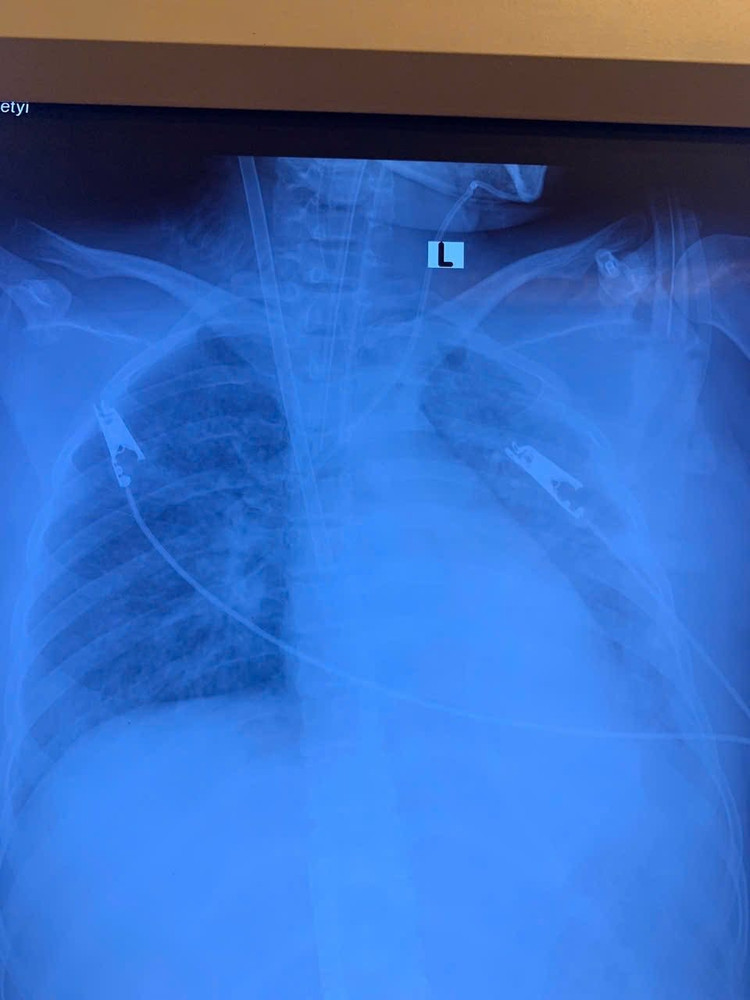

Bệnh nhân nữ, 19 tuổi, nhập viện trong tình trạng khó thở, sốt cao, ho đờm. Chẩn đoán ban đầu là viêm phổi nặng. Chỉ trong vòng 3 ngày, tình trạng hô hấp suy sụp nhanh chóng, hình ảnh X-quang và CT phổi cho thấy phổi trắng xóa hai bên – dấu hiệu điển hình của Hội chứng suy hô hấp cấp tiến triển (ARDS), một biến chứng nguy kịch thường gặp ở những ca viêm phổi nặng.

Hình ảnh tổn thương phổi trên phim chụp - Ảnh BVCC